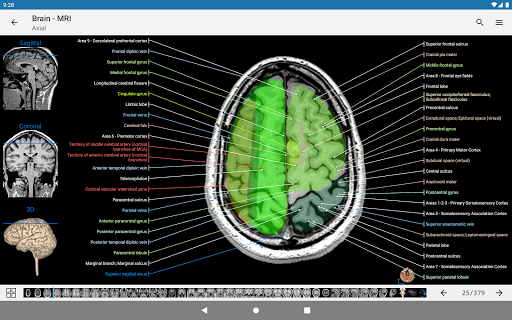

-The pins mode have a new behaviour allowing you to follow an anatomical structure much more easily

-Within the details view of an anatomical structure, a pin now points the related structure in all present images

Also tap directly on the image to navigate to the presented image in that module

- “Filter by”, in the details view you can now filter the images containing the anatomical structure by modality

- You can now hide structures one by one (new button inside the description popup) and display them again in the right menu